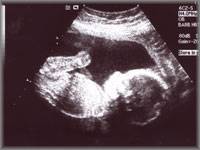

Ultrasound

imaging is a diagnostic medical technique that relies on marked differences in characteristic acoustic impedances. On the right is an ultrasound image of an unborn baby. Just like submarine sonar, reflected sound (echoes) are created due to the impedance mismatch – in this case between the body of the baby and the surrounding embryonic fluid. A gel is smeared onto the skin of the baby's mother to minimise energy reflection due to the large impedance difference between air and skin.